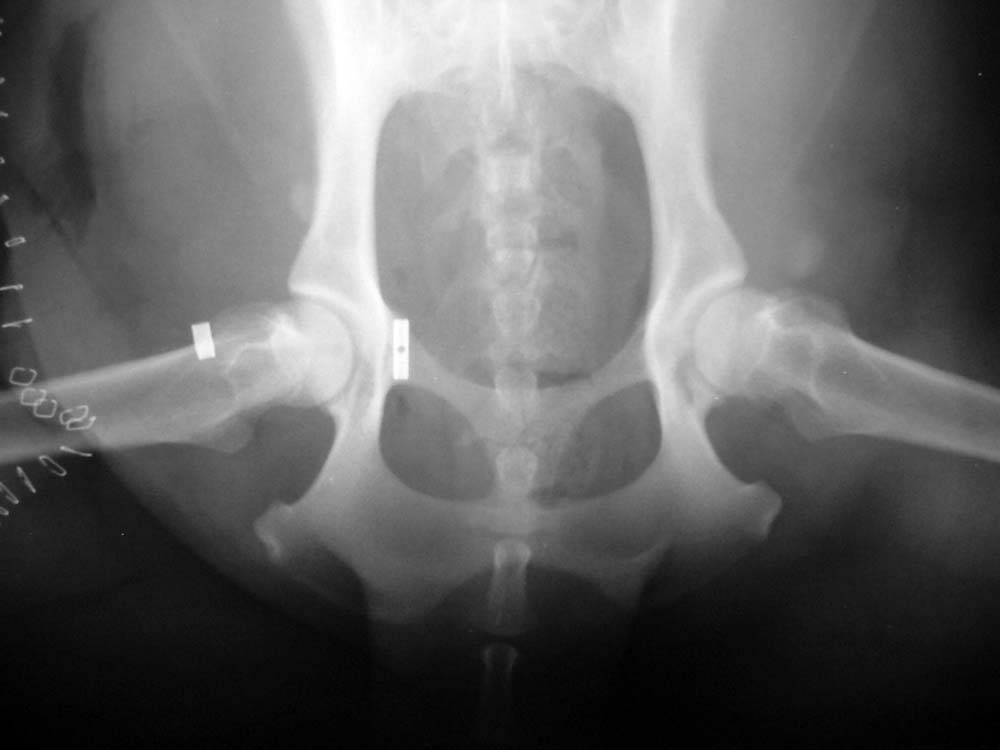

Hip dysplasia

Hip dysplasia (HD) is a common condition of dogs and also occurs occasionally in cats, particularly the larger pedigree cats. Hip dysplasia is abnormal development of the hip during the first few months of life. This starts with excessive laxity of the joint which leads to instability between the ball of the joint (the femoral head) and the socket (the acetabulum). That instability leads to secondary remodelling of the developing femoral head and acetabulum such that the femoral head becomes flattened and the acetabulum becomes shallow resulting in a poorly fitting joint. This poor fit eventually leads to secondary osteoarthritis. There are many dogs that have a degree of HD which is tolerated and does not cause clinical signs but some dogs are not so lucky and have pain associated with the dysplasia when they are young (typically 6-12 months of age). Probably more dogs end up with pain from secondary osteoarthritis even though they did not have obvious pain when they were young.